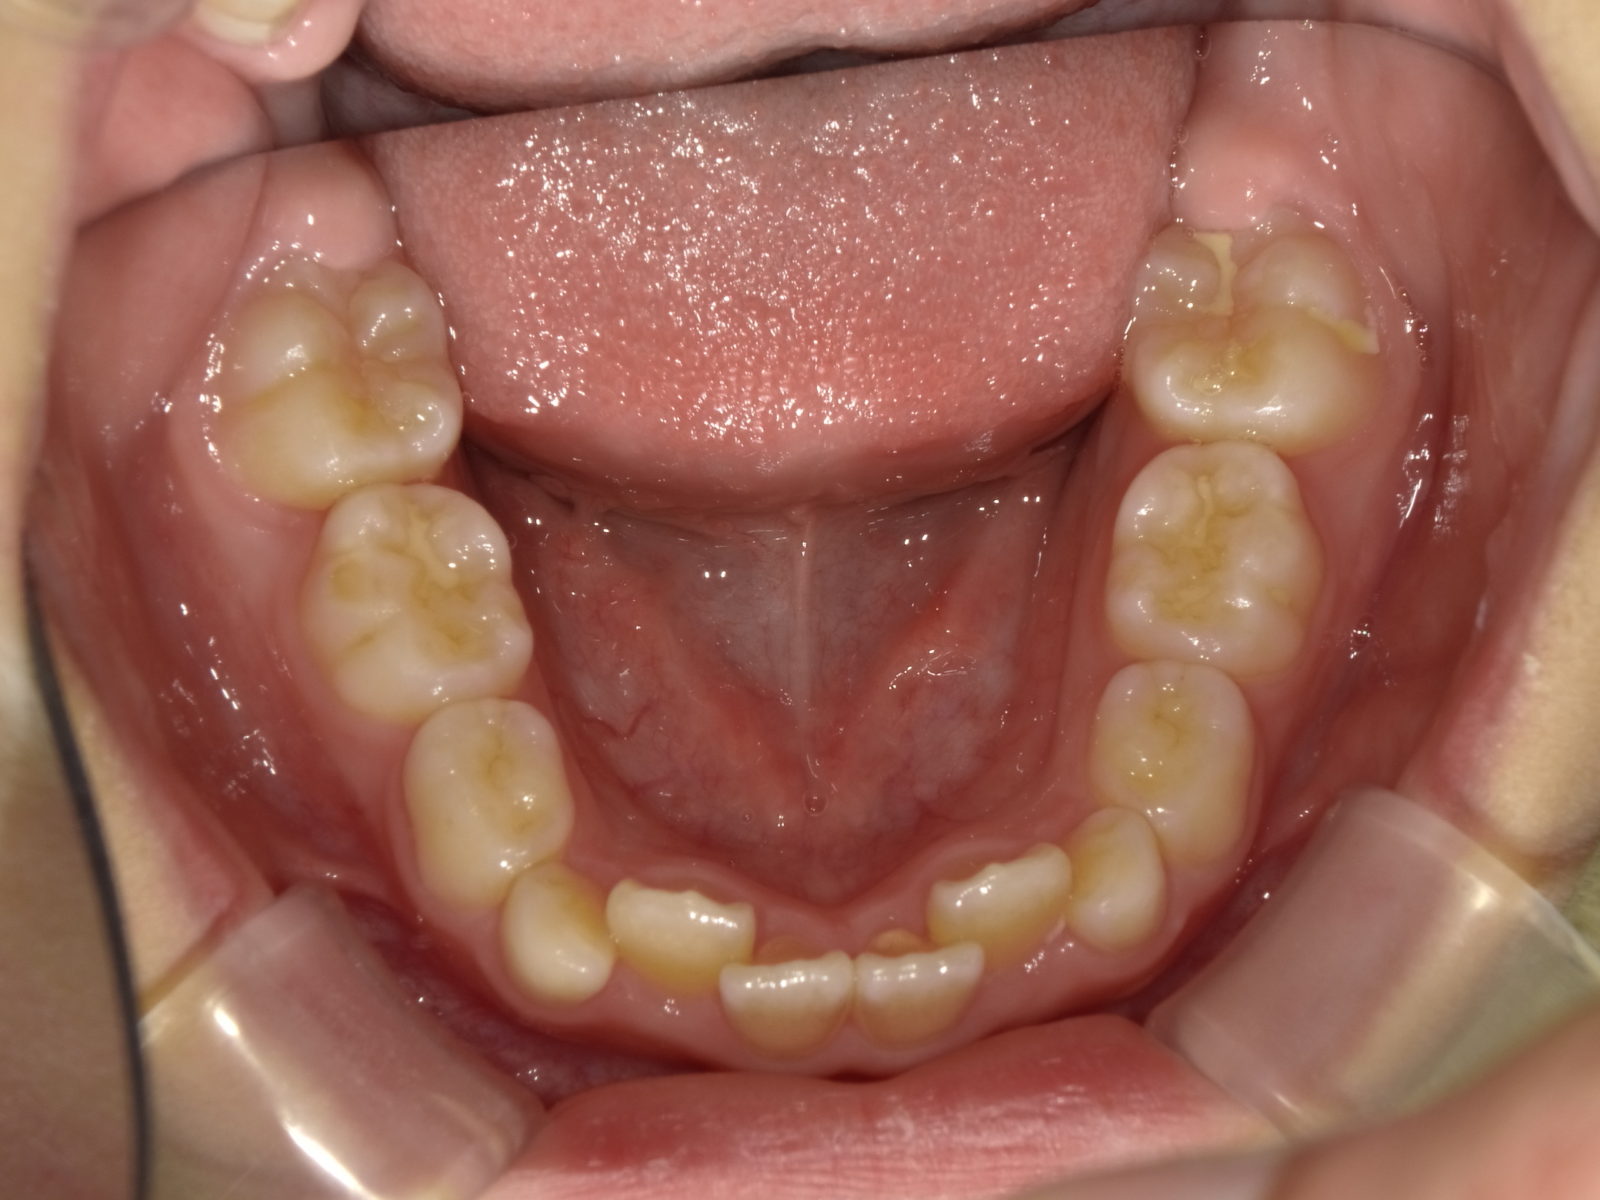

「マイオブレース」とは、従来のワイヤー矯正装置とは異なり、直接歯を動かすのではなく、歯並びを悪化させる口周りの筋肉の癖を改善することで間接的に歯並びを整えていく装置です。

歯の生え方は偶然ではなく、「舌・頬・唇の筋肉」の働きとそのバランスによって決まります。この口周りの筋肉のバランスが崩れていると、歯並びも乱れが生じますが、バランスが整っていれば、歯は理想的な位置に自然と並びます。

マイオブレースを装着することで、自然にこれらの筋肉を訓練し、バランスを整えることができます。歯は適切な位置に自然と並んでいくため、矯正治療においてより自然な方法で美しい歯並びを目指すことが可能になります。